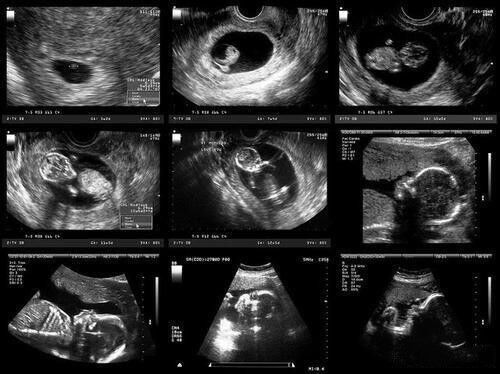

一般,如果查出怀孕比较早,比如刚出来只有4-5周,胚胎还很小,做腹部B超可能会看不清楚。

文章插图

为了检查效果好,看的更清楚,医生会让做阴超检查。尤其是较胖的孕妇,腹部脂肪较多,从腹部做B超可能会看不清。

但如果查出怀孕后,胎儿的孕周比较大了,做腹部B超也能清楚的看到,医院就大多让做腹部B超了。